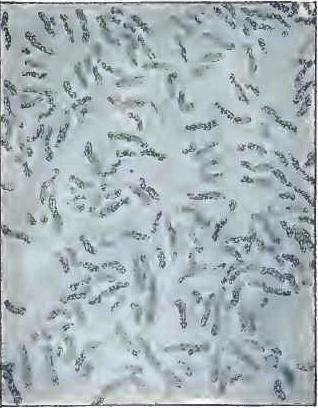

| FIGURE | |

| 1. | MICROCOCCI |

| 2. | BACTERIA |

| 3. | BACILLUS MALARIÆ |

| 4. | BACTERIA FROM GELATIN SOLUTION |

| 5. | VIBRIOS IN GELATIN CULTURE-FLUID |

| 6. | PROTOCOCCUS FROM SLIDES EXPOSED OVER SWAMP-MUD |

| 7. | BACILLI FROM SWAMP-MUD |

| 8. | BACILLI FROM SEPTICÆMIC RABBIT |

| 9. | BACILLI FROM HUMAN SALIVA |

| 10. | BACILLUS ANTHRACIS |

| 11. | BACILLUS TUBERCULOSIS |